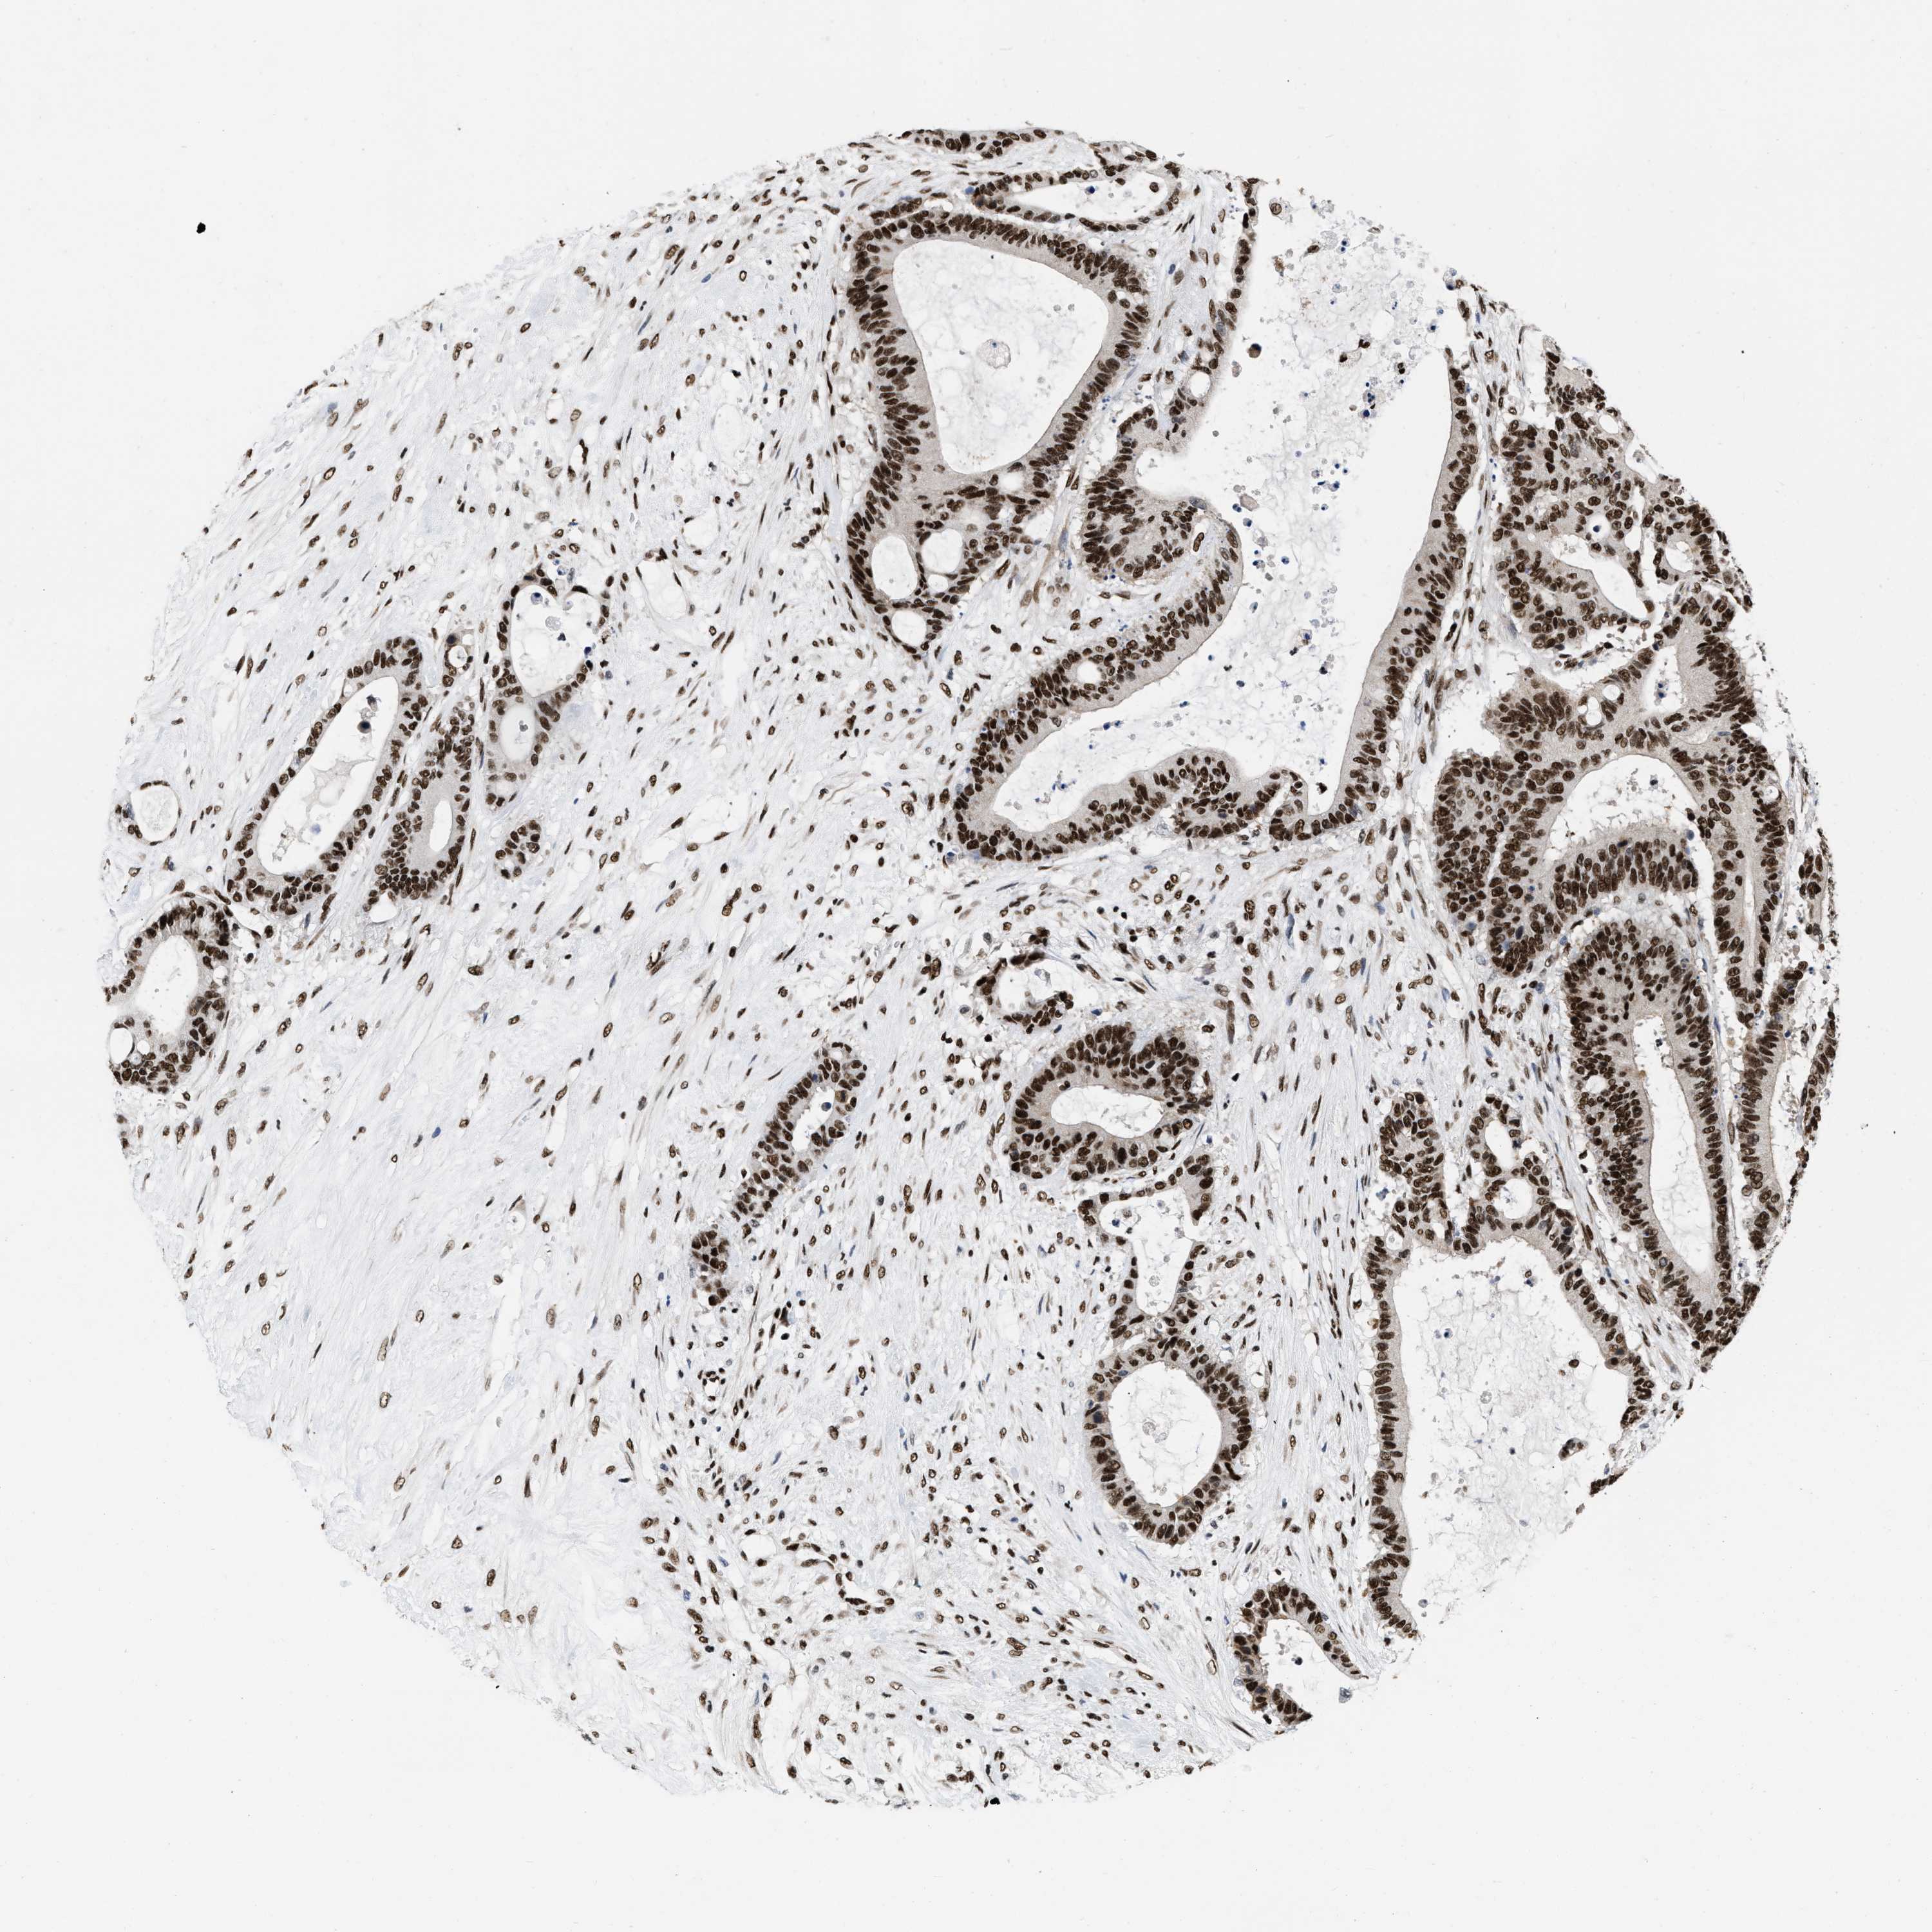

LIVER CANCER - Protein expressioni

A mouse-over function shows sample information and annotation data. Click on an image to view it in a full screen mode. Samples can be filtered based on level of antibody staining by selecting one or several of the following categories: high, medium, low and not detected. The assay and annotation is described here.

Note that samples used for immunohistochemistry by the Human Protein Atlas do not correspond to samples in the TCGA dataset.

Antibody stainingi

Antibody staining in the annotated cell types in the current human tissue is reported as not detected, low, medium, or high, based on conventional immunohistochemistry profiling in selected tissues. This score is based on the combination of the staining intensity and fraction of stained cells.

Each image is clickable and will lead to virtual microscopy that enables deeper exploration of all samples and also displays staining intensity scores, fraction scores and subcellular localization as well as patient and tissue information for each sample.

Antibody HPA019150

Antibody CAB003803

Staining

High

Medium

Low

Not detected

Intensity

Strong

Moderate

Weak

Negative

Quantity

>75%

75%-25%

<25%

None

Location

Nuclear

Cytoplasmic/membranous

Cytoplasmic/membranous,nuclear

Cholangiocarcinoma

Carcinoma, Hepatocellular, NOS